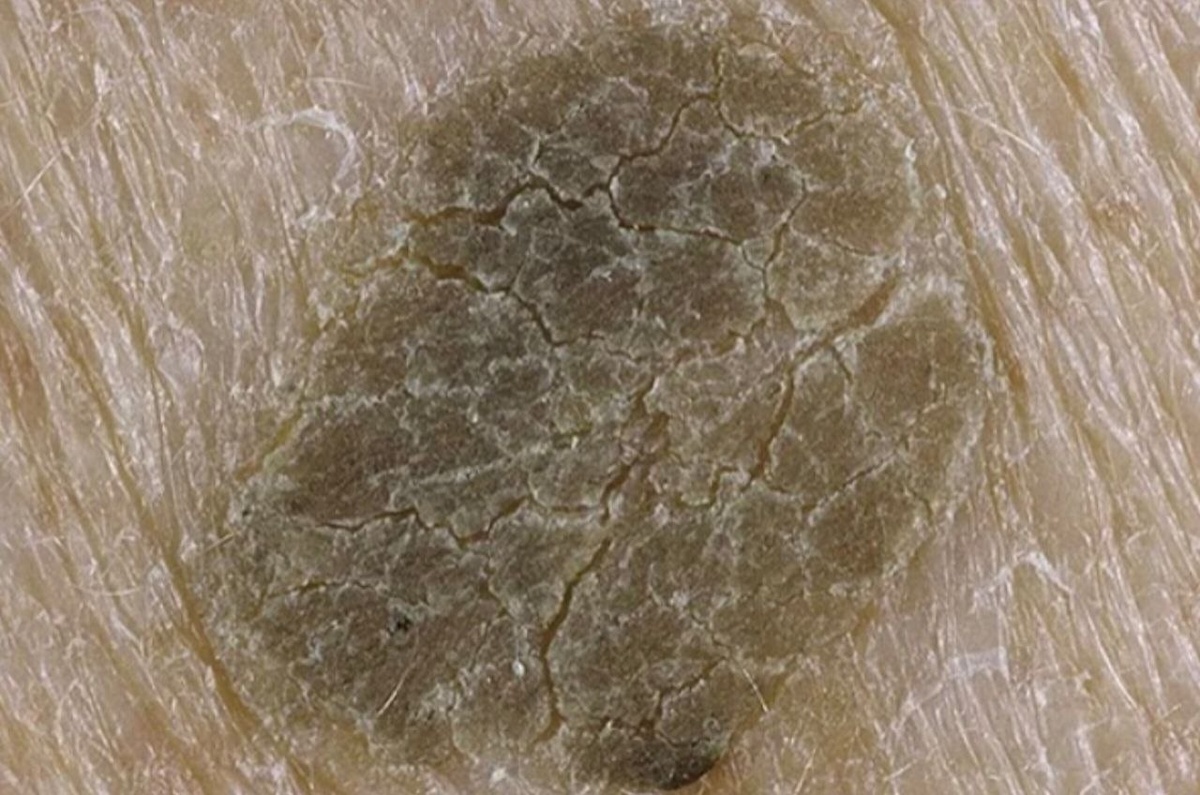

Кератома — это как «ошибка в программе» старения кожи. В каком-то месте клетки начинают слишком активно роговеть и накапливаться. Они не хотят отваливаться, а сбиваются в плотную, сухую, шершавую «лепешку». Чаще всего это:

Цвет — от телесного до темно-коричневого.

Поверхность — шершавая, покрыта трещинками или жирными корками (как будто прилипло что-то).

Ощущения — обычно никаких. Иногда чешется, если зацепить одеждой.